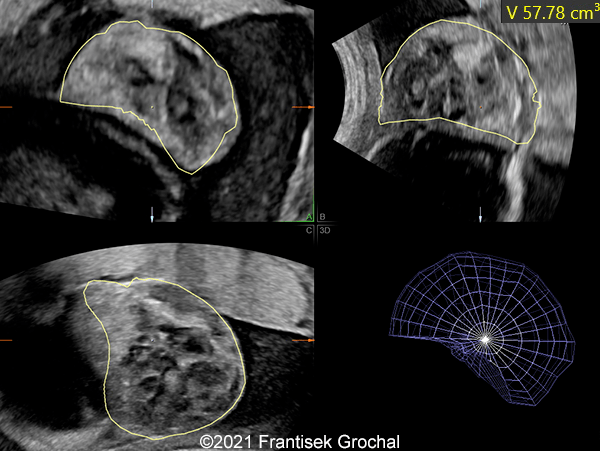

Case Report: A 24-year-old secundigravida, primipara presented to our office at 24 weeks and 6 days of her pregnancy due to a right-sided cranial parieto-occipital mass of the fetus. We obtained the following images.

Our ultrasound images at 24 weeks, 6 days show a highly vascularized, mostly solid mass measuring 58 x 45 x 34mm in the right-parieto-occipital subcutaneous region. Vascular supply of the lesion could be traced to the right vertebral artery. Repeat ultrasound exams done later in pregnancy demonstrated that the size of the mass remained stable with overall mass volume about 58 cm³.